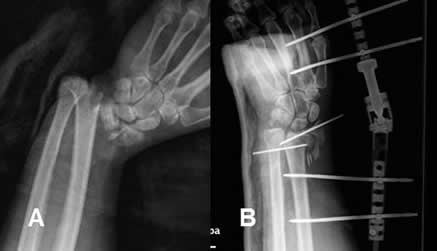

Fig 83. Reducción cerrada.

A: Rx lateral. Fractura del radio distal, con angulación anterior.

B: Rx lateral. Luego de la reducción, se estabiliza con yeso.